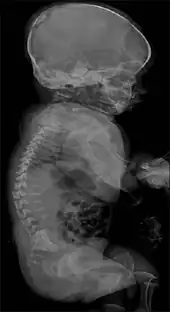

It is a lethal rhizomelic (malformations which result in short, underdeveloped limbs) form of dwarfism,[1] exhibiting both skeletal dysplasia (malformations of bone) and fibroblastic dysplasia (abnormal development of fibroblasts, specialized cells that make up fibrous connective tissue, which plays a role in the formation of cellular structure and promotes healing of damaged tissues).[4][5][6] Death caused by complications of fibrochondrogenesis occurs in infancy.[6]

Fibrochondrogenesis is a congenital disorder presenting several features and radiological findings, some which distinguish it from other osteochondrodysplasias.[7] These include: fibroblastic dysplasia and fibrosis of chondrocytes (cells which form cartilage);[4][5] and flared, widened long bone metaphyses (the portion of bone that grows during childhood).[6][8]

Other prominent features include dwarfism,[1] shortened ribs that have a concave appearance,[6] micrognathism (severely underdeveloped jaw),[7] macrocephaly (enlarged head),[8] thoracic hypoplasia (underdeveloped chest),[8] enlarged stomach,[8] platyspondyly (flattened spine),[6] and the somewhat uncommon deformity of bifid tongue (in which the tongue appears split, resembling that of a reptile).[7]